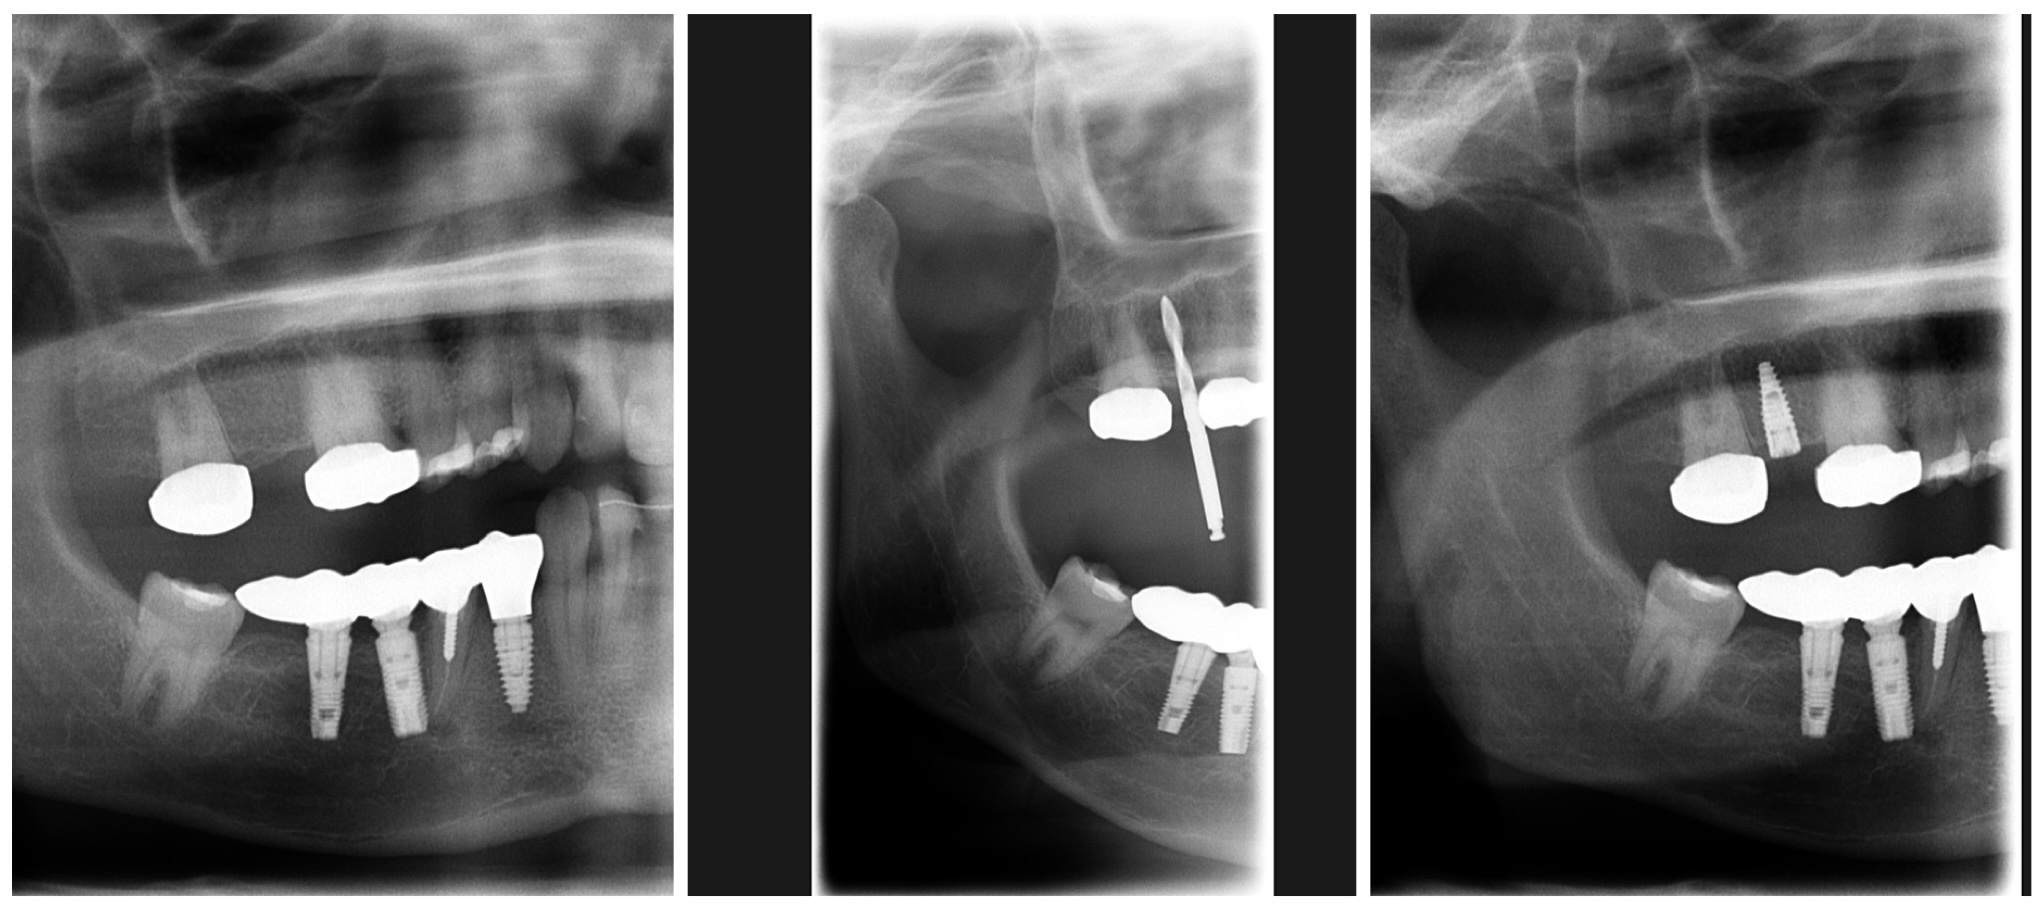

Book an Appointment (Bella Dent Dental Center)